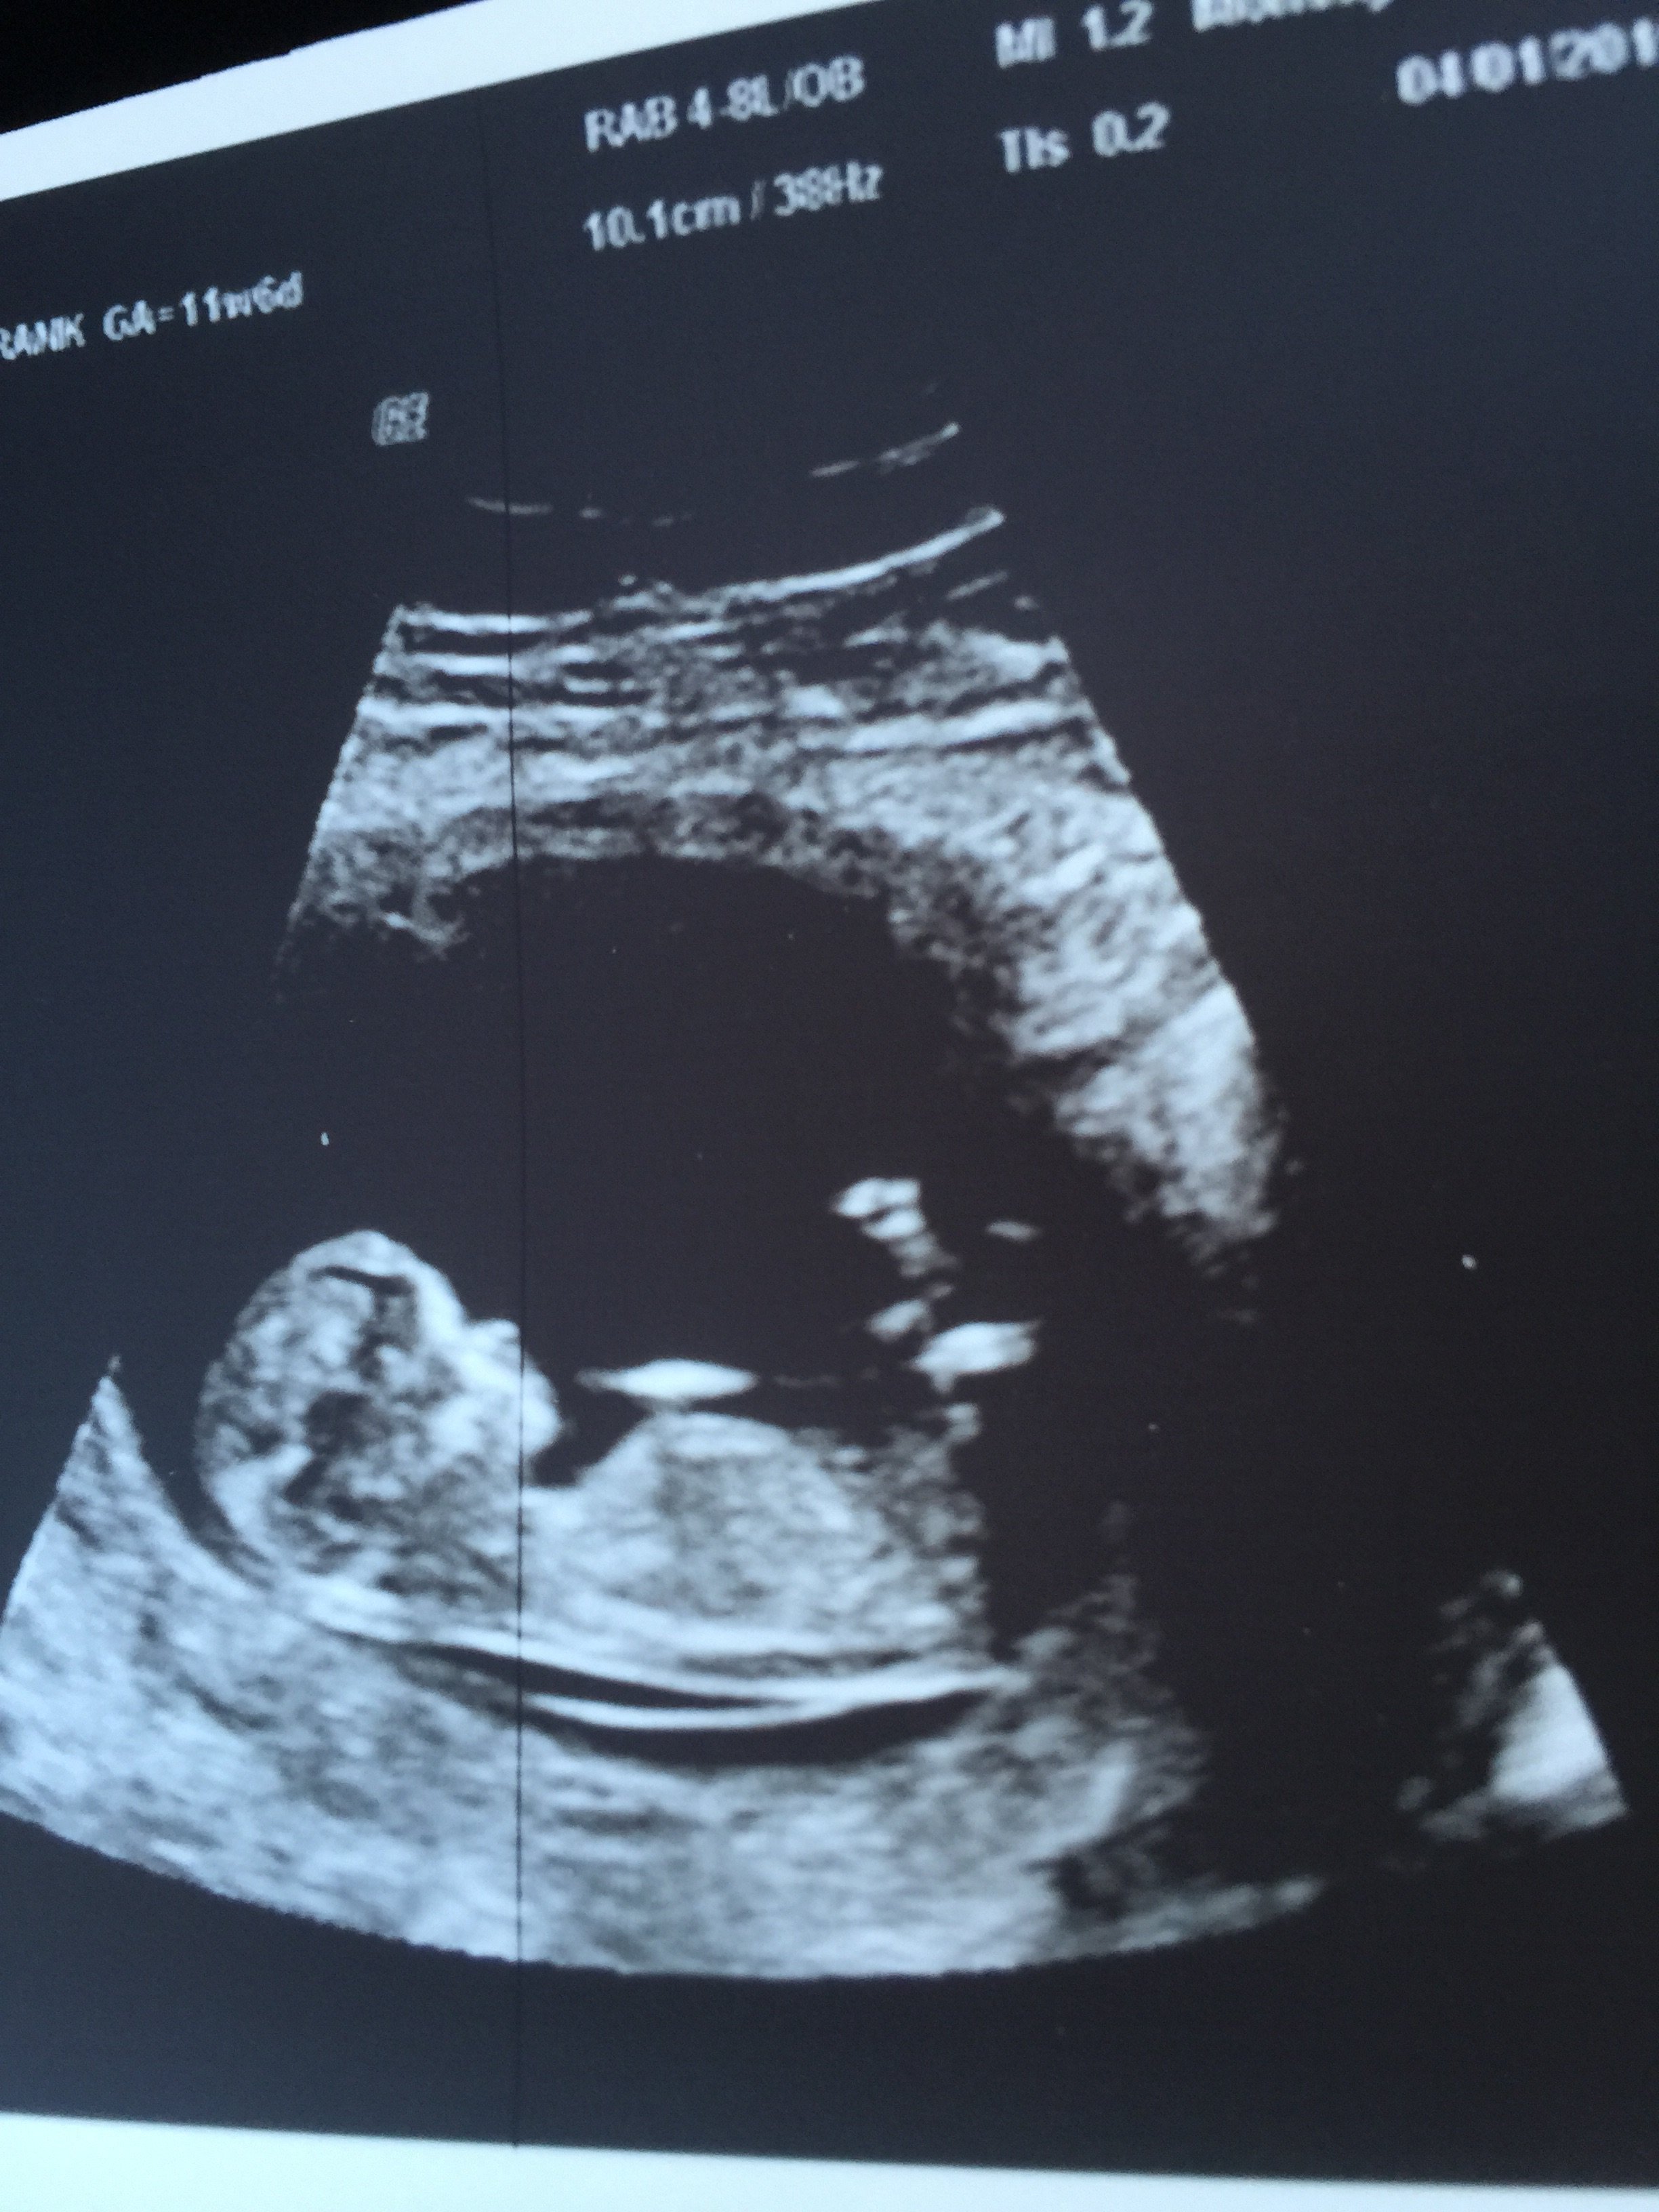

Here is my most recent ultrasound pic. It was great to get an abdominal scan this time and their gel was warm! Our little pumpkin was moving all over the place with a heart rate of 164! I brought my mom and she got a great kick out of seeing it all! This was 11w6d.